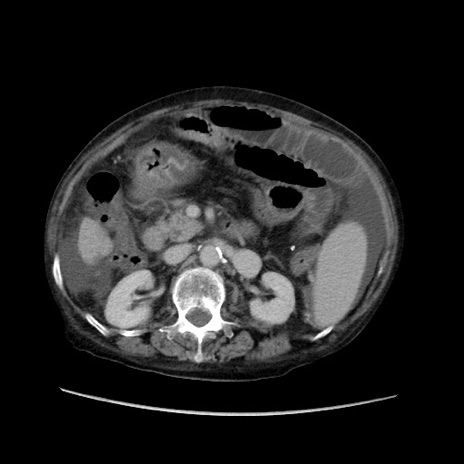

症例31(横断像)

【症例】80歳代 女性

【主訴】腹部膨満感

【現病歴】他院にて肝硬変にてフォロー中。1週間前から便秘、腹部膨満感、臍部腫瘤あり受診となる。

【既往歴】肝硬変

【身体所見】腹部膨隆あり、皮膚変化なし、疼痛なし。

【データ】WBC 4600、CRP 0.25